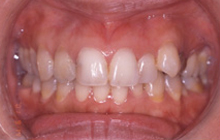

(治療前:写真左)

態癖の影響が強く奥歯が舌側に傾斜し、八重歯になっています。